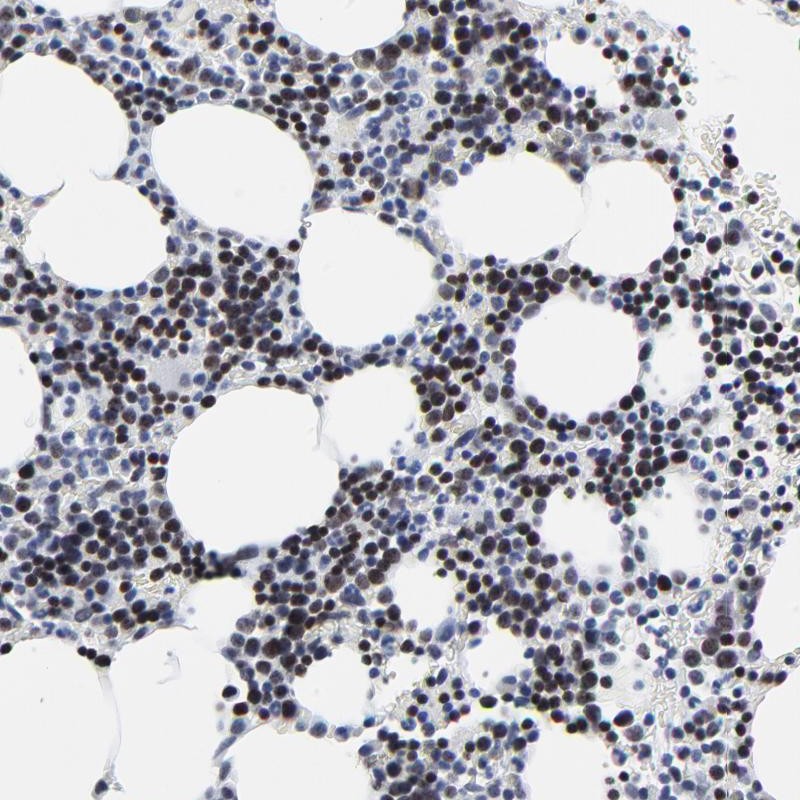

Immunohistochemical staining of human bone marrow shows strong nuclear positivity in bone marrow poietic cells.